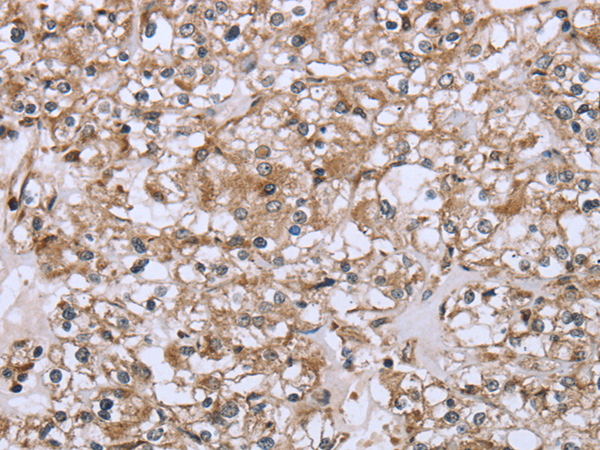

IHC positive control:

Human liver cancer and Human prostate cancer